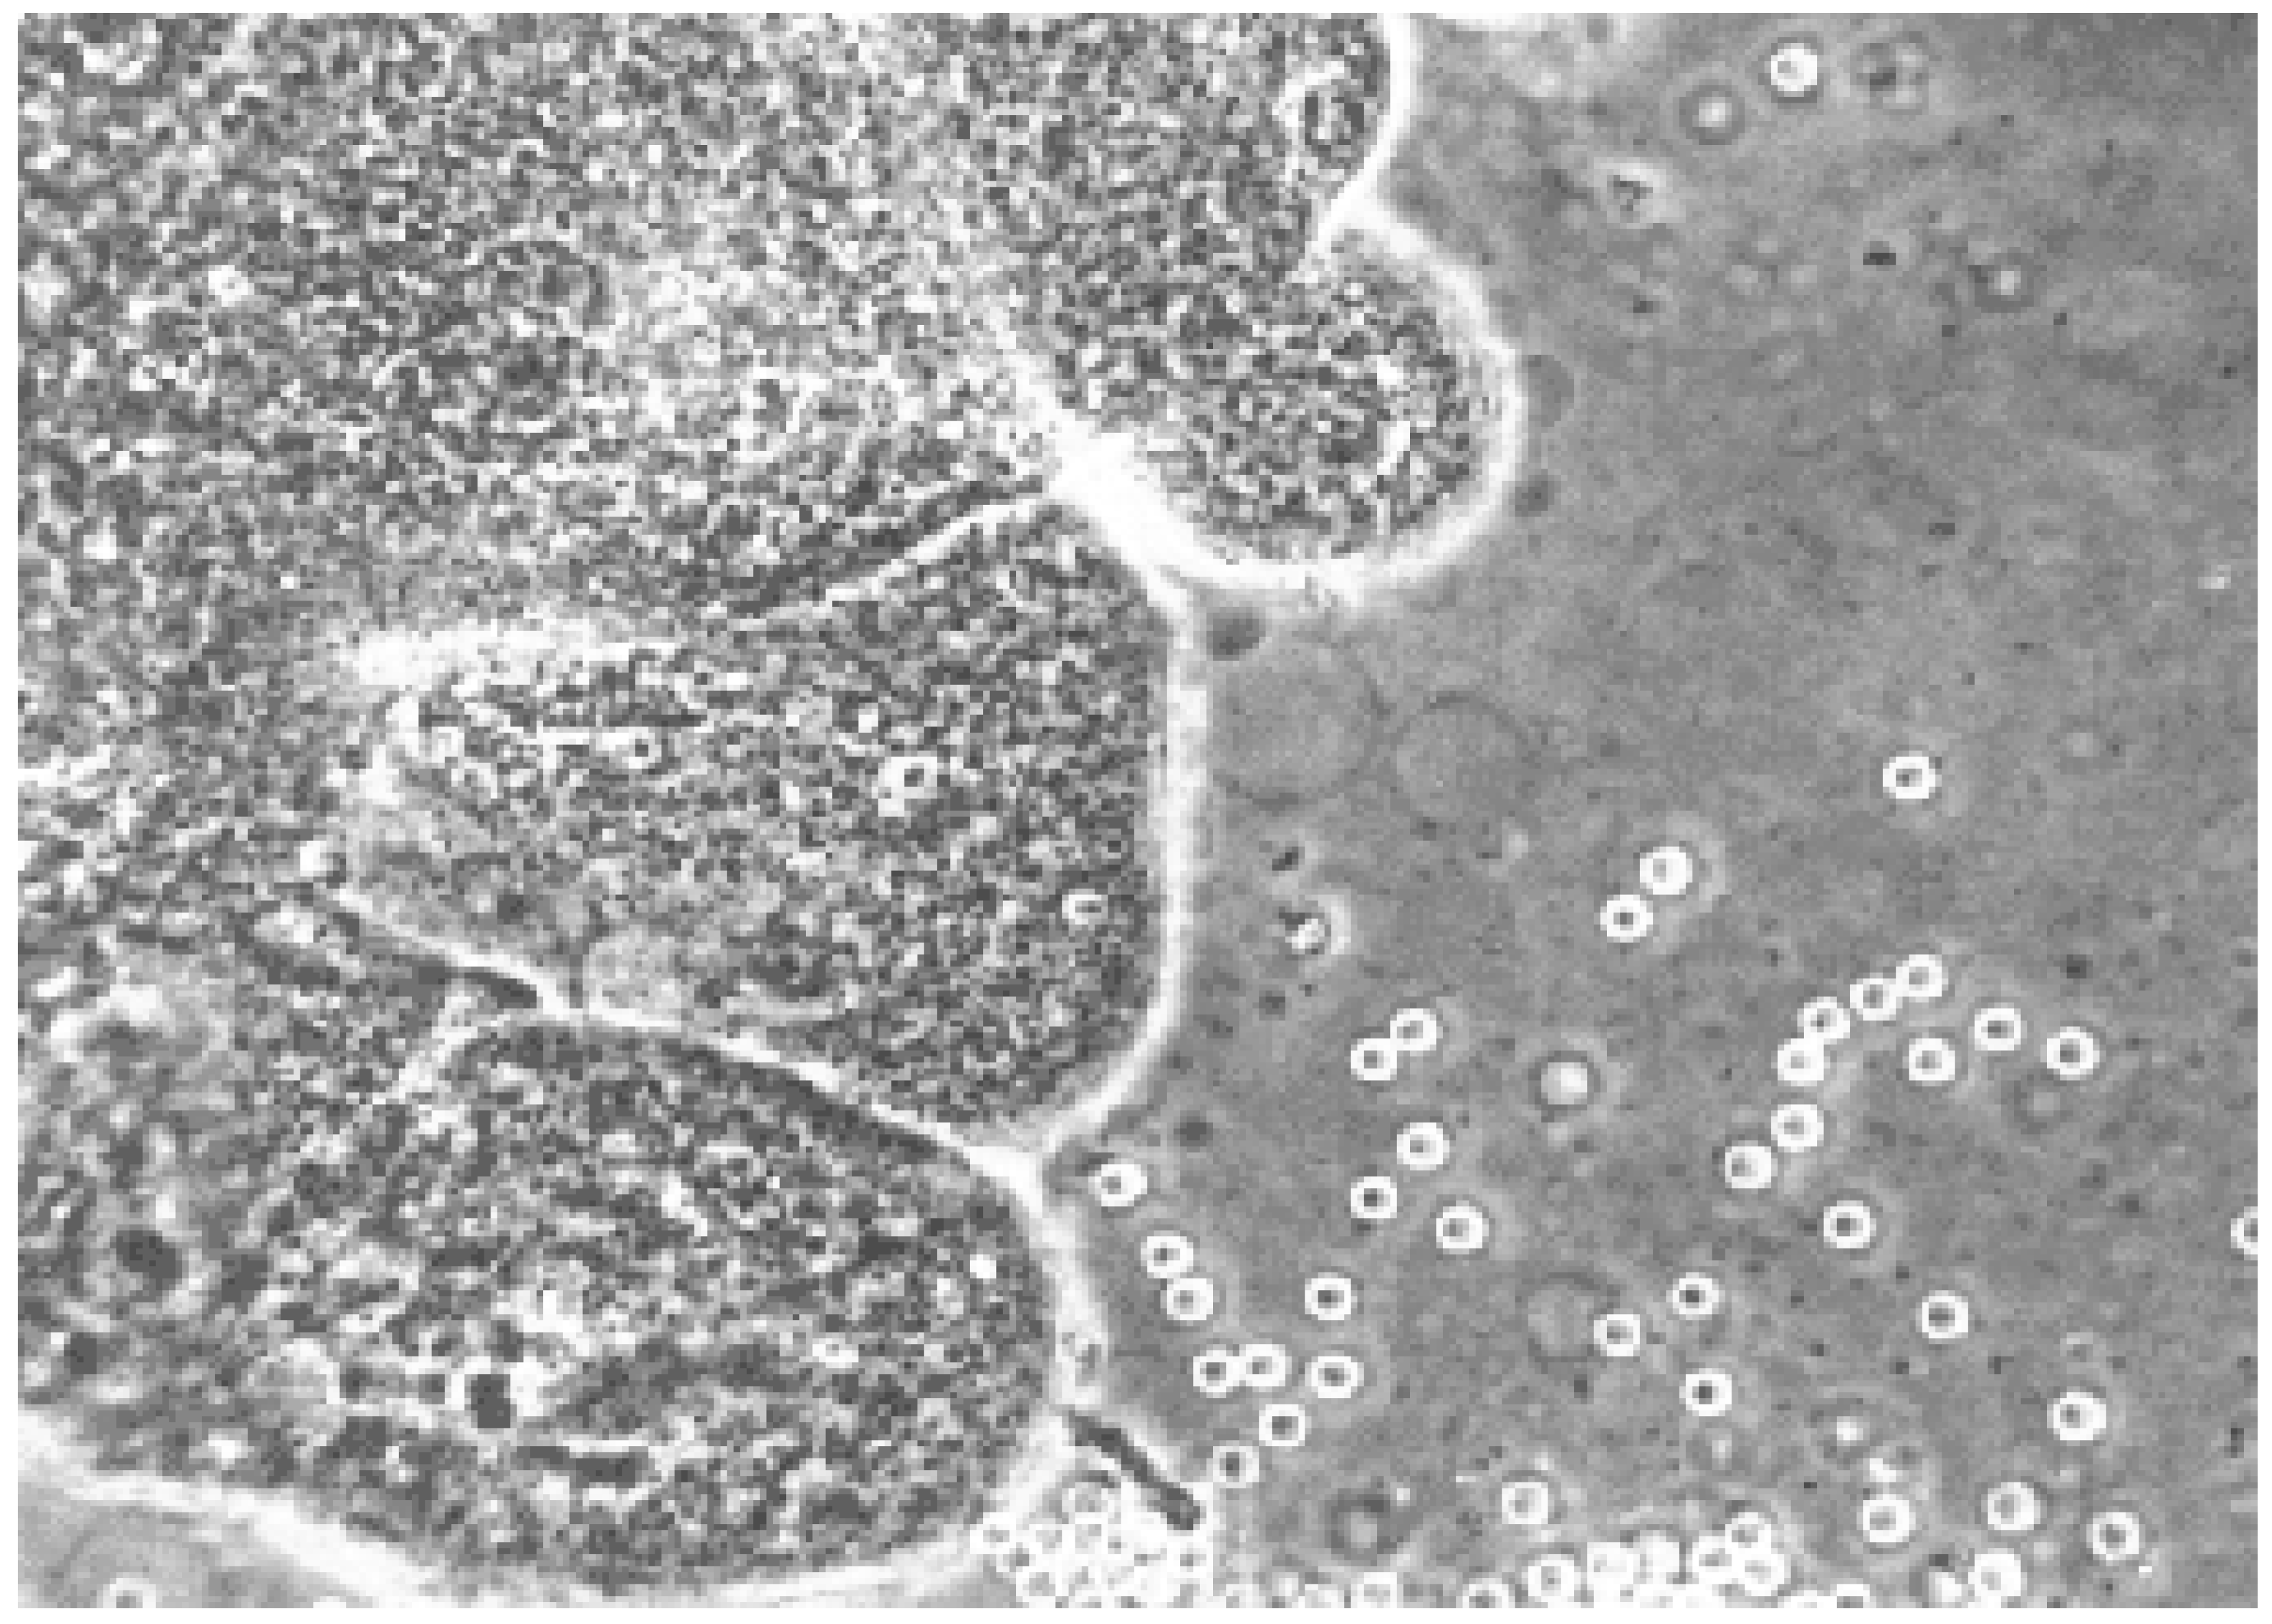

The collected villus tissue samples were promptly transported to the laboratory and examined under a dissecting microscope (Figure 2), following established protocols described in the literature [1,2,3,4,6,8,10,11,12,13,19,20,21,22,23,26]. For cytogenetic analysis, either an overnight short-term incubation (approximately three days) or a standard seven-day culture method was employed. In all cases, fetal heart rate (FHR) was assessed before and after the procedure using M-mode ultrasonography. In a subset of 200 patients, alpha-fetoprotein (AFP) levels were measured 10 min before and 10 min after the CVS procedure to assess the presence of feto-maternal hemorrhage.

Figure 2.

Chorionic villus tissue observed under a dissecting microscope. Source: Authors.